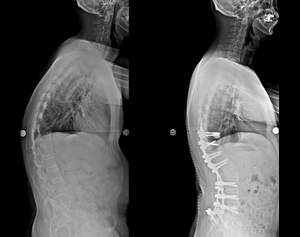

病例一 |

| 術前 |

術後 |

| 側向X光片 |